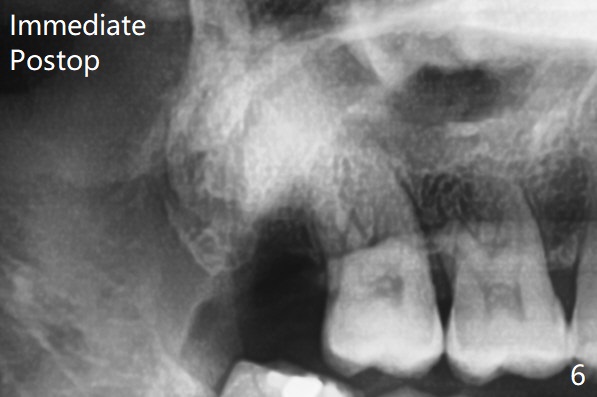

The bone density is high post #1 extraction (Fig.6 (left panel)), related to difficult removal (DB root tip fracture). It appears that bone graft at #16 (^) remains in place 15 months postop.